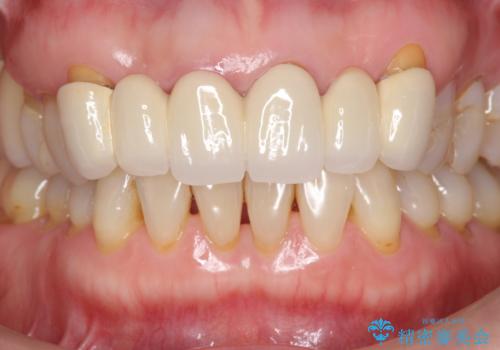

不自然な前歯ブリッジ ジルコニアブリッジによるやり替え

- 20年前に入れたブリッジの見た目の改善を求めて来院されました。

丁寧に現在装着されているブリッジを除去後、精度の高いジルコニアブリッジで審美性の改善を計画します。

- 66万円(仮歯・ジルコニアクラウン×6)費用は治療当時の料金となります

前歯に限らず拡大鏡を用いた精密な形成・シリコンを用いた精度の高い印象を徹底することで治療全体の質を高め、審美性だけでなく長期的な予後を期待することができます。